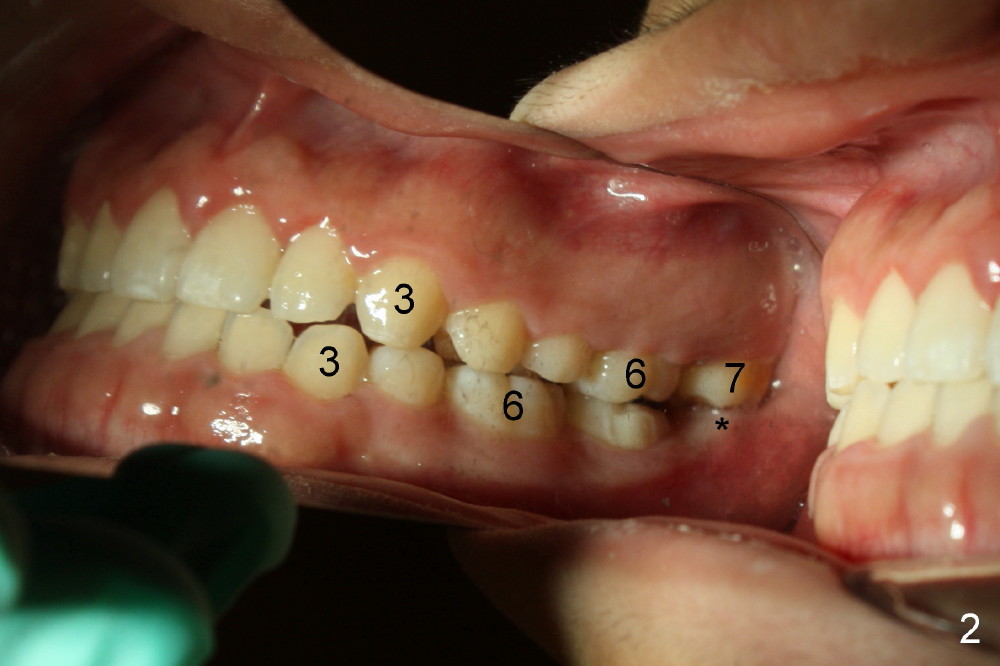

打完下颌神经麻药,乘麻药还没有奏效,拍摄图二至图五,图二,图三显示前牙第一类咬合,而后牙第三类,上颌第二磨牙(7)咬在下颌牙龈(*,仿佛形成白斑(leukoplakia))。图四,图五显示上颌第二磨牙向下伸长。那时我还不具有力挽狂澜能力。那么这四个智齿该拔吗?